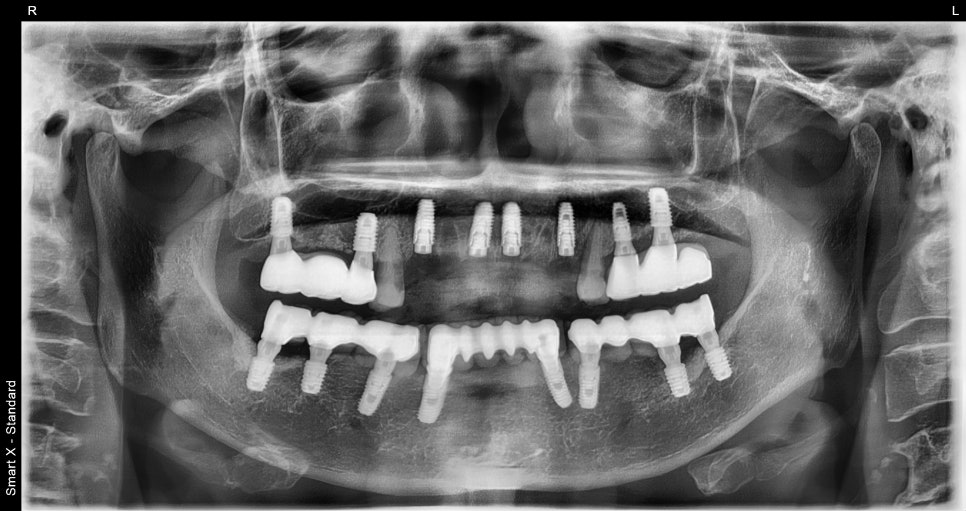

초진내원당시

이번 환자분은 65세 여성으로

위 앞니가 여러 개 상실된 상태로 내원하셨습니다.

발치와 동시에 진행된 임플란트 식립

이번 케이스에서는

손상된 앞니를 발치한 후

임플란트 식립이 동시에 진행되었습니다.

✔ 전치부 다수 임플란트 식립

✔ 골유도재생술(GBR) 진행

✔ 동종골 이식 병행

앞니는 뼈가 얇기 때문에

뼈이식

이 함께 진행되는 경우가 많습니다.